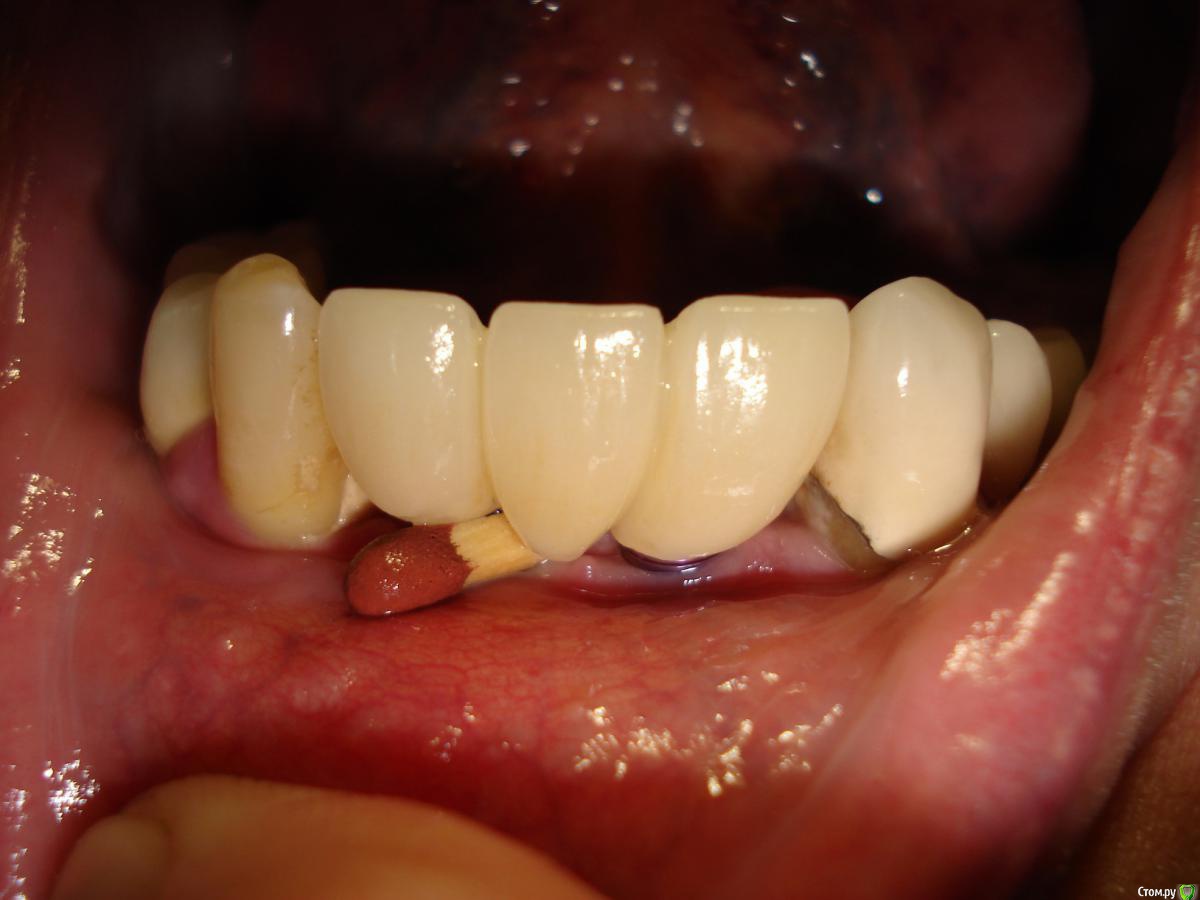

Antikwar Опубликовано 26 ноября, 2017 Поделиться Опубликовано 26 ноября, 2017 Доброго времени суток .Хотелось бы узнать компетентное мнение, врачей, З.техников. Вчера было установленно 2 моста (оксид циркония) на имплантанты перед низ и 2 коронки с боку правая сторона низ ..НА мой не опытный взгляд конструкция и сама работа не качественная и эстетика здесь полностью отсутствует. 1.Видно тело абатмента в обоих конструкциях. 2.Мост и коронки висят в воздухе и не прилегают к десне,как в первом так и во втором случае. Между десной и мостом (перед низ) проходит спичка. Вопрос, должен ли мой доктор переделать эту (на мой взгляд) не качественную работу ! Что вы мне посоветуете .... Заранее благодарю всех откликнувшихся. Ссылка на комментарий

chervoncevdaniil Опубликовано 26 ноября, 2017 Поделиться Опубликовано 26 ноября, 2017 Доброго времени суток .Хотелось бы узнать компетентное мнение, врачей, З.техников. Вчера было установленно 2 моста (оксид циркония) на имплантанты перед низ и 2 коронки с боку правая сторона низ ..НА мой не опытный взгляд конструкция и сама работа не качественная и эстетика здесь полностью отсутствует. 1.Видно тело абатмента в обоих конструкциях. 2.Мост и коронки висят в воздухе и не прилегают к десне,как в первом так и во втором случае. Между десной и мостом (перед низ) проходит спичка. Вопрос, должен ли мой доктор переделать эту (на мой взгляд) не качественную работу ! Что вы мне посоветуете .... Заранее благодарю всех откликнувшихся.СУдя по фото у вас убыль костной и мягких тканей в области ипмлантов.А состояние соседних коронок на зубах вас не смущают? Ссылка на комментарий

krokomot Опубликовано 27 ноября, 2017 Поделиться Опубликовано 27 ноября, 2017 целевая зона на снимке замылена, четкости нет, исходя из ваших фотографий проблемма не в коронках, а в позиции имплантатов - видна шейка имплантата, так быть не должно. нужны прицельные снимки этой области. Учитывая обстоятельства коронки изготовливаются исходя из положения имплантатов.и я так понимаю вас запротезировали из позиции то что есть, и вая явно нужно что-то делать. Ссылка на комментарий